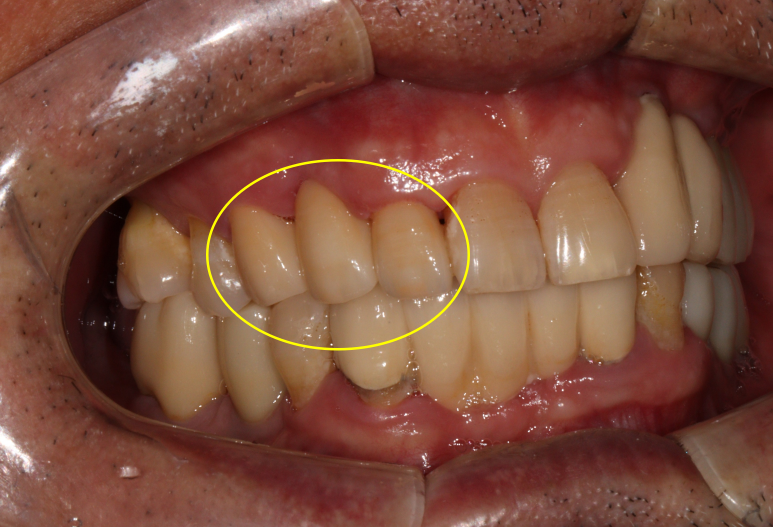

임플란트가 무려 9개나 되어있네요! 여기에서 앞니 임플란트의 명백한 단점을 확인할 수 있습니다.

보이시나요? 바로 임플란트 크라운이 너~무 길다는 것.

잇몸질환 (만성 치주염)이 심하신 분들의 경우 잇몸뼈의 상실이 심해 결국 임플란트를 '깊게' 심게 됩니다.

결과적으로 치아 길이가 너~무 길어보여 결국 음식도 많이 끼고 비심미적인 (보기 안 좋은) 결과를 낳는다는 것...

사실 어쩔 수 없이 임플란트를 해야만 하는 상황이긴 하나, 잇몸뼈 염증이 심했을 땐 저렇게 어색한 임플란트 머리를 피할 수가 없습니다...

이런 경우 저는 단호하게 앞니 임플란트 말고 앞니 브릿지를 권해드립니다.

그 이유가 앞에 나왔죠? 잇몸뼈를 너무 많이 잃어버린 상황에서 임플란트를 억지로 하면 임플란트 크라운이 너무 길어져 보기에도 안좋고 음식도 많이 끼고 결과적으로 임플란트 주위염에 시달릴 것이 뻔하기 때문이죠.

보시면 치아의 병적 이동으로 이미 자기 자리에서 한참 이탈해버린 오른쪽 위 송곳니를 보실 수 있습니다.

보이시는 것처럼 엄청나게 깊이 임플란트를 심어내고 결국 머리가 엄청 길어져버린 임플란트를 만들어드리게 된단 말이죠...